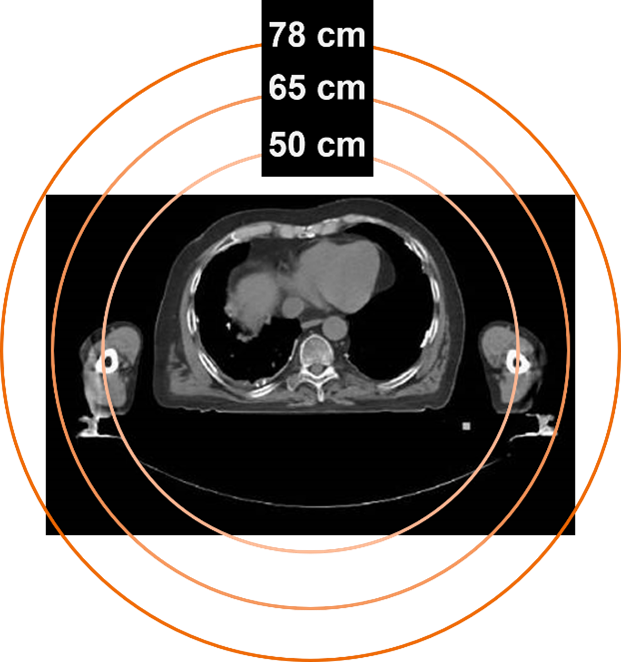

業界獨家78cm大孔徑

西門子采用業界獨家的78cm大孔徑PET/CT,相比于傳統70cm孔徑,78cm大孔徑短機身一體化的設計,提升了約25%的孔徑內空間。25%的孔徑內空間提升一方面可以滿足更大體型,特別是肥胖人群的日常掃描需求,提高了患者檢查的舒適度;另一方面,更大的有效視野和擺位空間也滿足了放療定位時的多種擺位要求。

西門子PET/CT不僅僅是PET系統的大孔徑,更是PET與CT一體化的78cm大孔徑,這使得該設備還可作為單獨的CT模擬機使用,一次患者掃描獲得PET/CT與CT增強定位圖像,極大地減少了兩組圖像間患者的體位誤差,靶區勾畫結果更為準確。

78cm HD高清視野(FOV)

基于獨家的78cm大孔徑,西門子推出了78cm HD高清視野(FOV)重建技術,與傳統的50cm CT重建視野相比,實現了全CT視野可見,能完全覆蓋所有人群的全部身體部位,同時完全兼容各種外展位、大體積放療支架等。